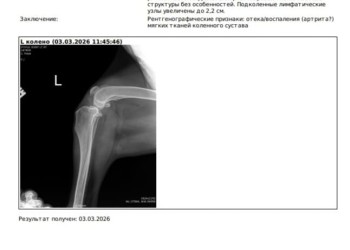

Ей нужна операция Артроскопия на левом коленном суставе (разрыв связки) с вероятностью постановки пластины.

Увы, разрыв связки можно устранить только хирургческим путем. Без операции мы со временем потеряем лапу и возможность жить полноценной жизнь.